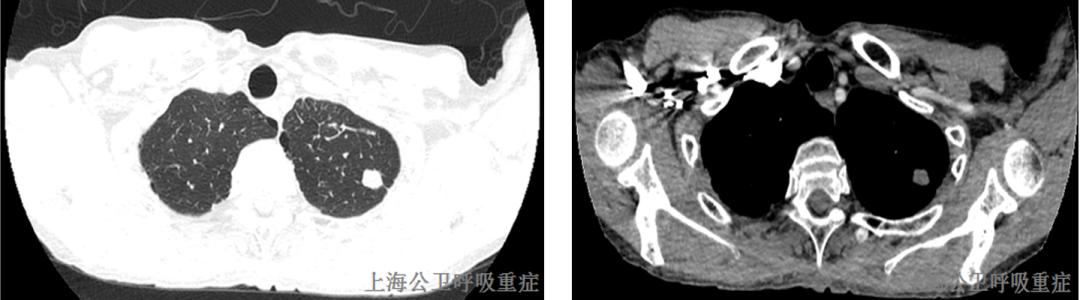

2020-10-02行胸部CT示:左侧气胸,左肺压缩约10%;左上肺结节,左下肺炎症,左侧胸腔积液,予口服左氧氟沙星抗感染治疗后症状无改善。2020-10-12外院复查胸部CT示:左肺散在感染灶可能,左侧液气胸,双肺尖胸膜下少许肺大泡。2020.10.15至我院就诊,门诊以“肺部感染伴液气胸”收入我科。

2020.10.22胸部CT增强示:左上肺尖后段、左上肺前段、左下肺前基底段及外基底段实性结节,左肺散在炎症,左侧胸膜局灶性增厚,左侧胸腔少量积液,左下肺部分膨胀不全;MT待排,请结合临床并进一步检查。左侧肺门淋巴结肿大。两上肺胸膜下小肺大泡。